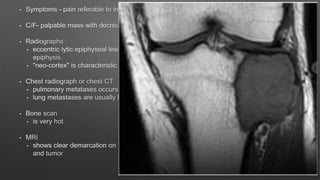

Giant Cell Tumor

• A benign aggressive tumor typically found in the metaphysis of long bones

• Age & sex

• more common in females

• ages 30-50 years

• Location

• distal femur > proximal tibia > distal radius > sacral ala

• distal radius is third most common location

• phalanges of the hand is also a very common location

• Malignancy

• primary malignant giant cell tumor

• metastatic to lung in 2-5%

• hand lesions have greater chance of metastasis

• Molecular biology

• Type II and III cells have IGF-I and IGF-II activity

• RANK pathway is important - denosumab acts on this pathway

• Nonoperative

• Radiation alone

• only indicated for inoperable or multiply recurrent lesions

• leads to 15% malignant transformation

• Medical management

• used to augment or replace surgical management

• medications

• bisphosphonates - osteclast inhibitors which may decrease the size of the tumors

• denosumab

• monoclonal antibody against RANK-ligand

• recent clinical trials suggest denosumab can decrease the size of tumor

• 90% tumor necrosis

• shows dramatic sclerosis and reconstitution of cortical bone after treatment